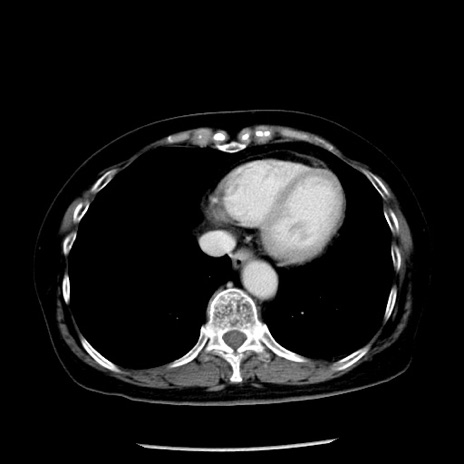

症例13(横断像)

【症例】70歳代女性

【主訴】腹痛、嘔吐

【現病歴】15時間程前(昨晩)より腹痛あり。今朝になっても症状の改善なく、嘔吐あり。腹痛も増悪あり、救急外来受診。

【既往歴】子宮癌全摘術後

【身体所見】意識清明、BP 121/72mmHg、P 74bpm、SpO2 100%(RA)、腹部:平坦・軟、腸雑音ほぼ聴取せず。下腹部・心窩部・臍左上に圧痛あり。反跳痛なし。

【データ】WBC 10600、CRP 0.15